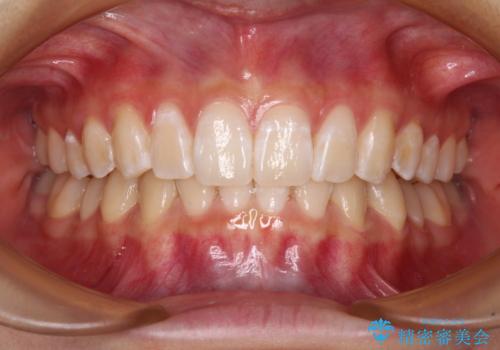

ディープバイトや奥歯の咬み合わせなど、インビザライン矯正では限界がありワイヤー装置での治療に及ばない仕上がりとなりました。

ただし、患者様としては八重歯や、それに伴う唇の閉じにくさが改善されたとのことで、納得いく状態での治療終了となりました。